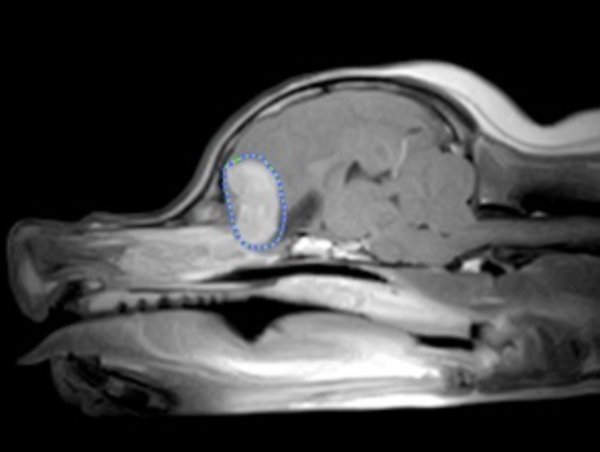

それ以降、月1回のペースでこの発作が続きました。次第にペースが上がってきたため、MRI検査をすると、脳腫瘍だと判明。このまま摘出手術を行なわないと発作は続き、死に至ることもあるとお医者さんから宣告されました……

みんなに笑顔を与えてくれる小さな家族、サラは2016年の5月から痙攣発作が起きるようになりました。突然倒れて手足バタバタ、口から泡をふき、意識が戻ると錯乱して動き回ります。月1回のペースで発作が続き、山梨県のかかりつけの動物病院の獣医さんに、検査、経過観察で診てもらっていましたが、次第に発作のペースが多くなったため、12月に原因を究明すべく先生の紹介で埼玉県の日本小動物医療センターに行きMRI検査を受けることになりました。

検査結果は脳腫瘍でした。このとき、このまま摘出手術を行なわないと発作は続き、死に至ることもあるとお医者さんから宣告され、とてもショックでした…。検査費用だけでも12万円もかかり、この時点で費用捻出は限界の状態です。さらに、手術代の100万円がかかってはと…。

現在はクスリで何とか大きな発作は抑えられていますが、元気がなく、横たわっている時間が長い状態です。今回のプロジェクトでサラの手術を行います。手術の内容は、頭蓋内腫瘤摘出術、脳内の腫瘍を取り除くものです。また、手術の前後で入院治療(検査)が必要になります。